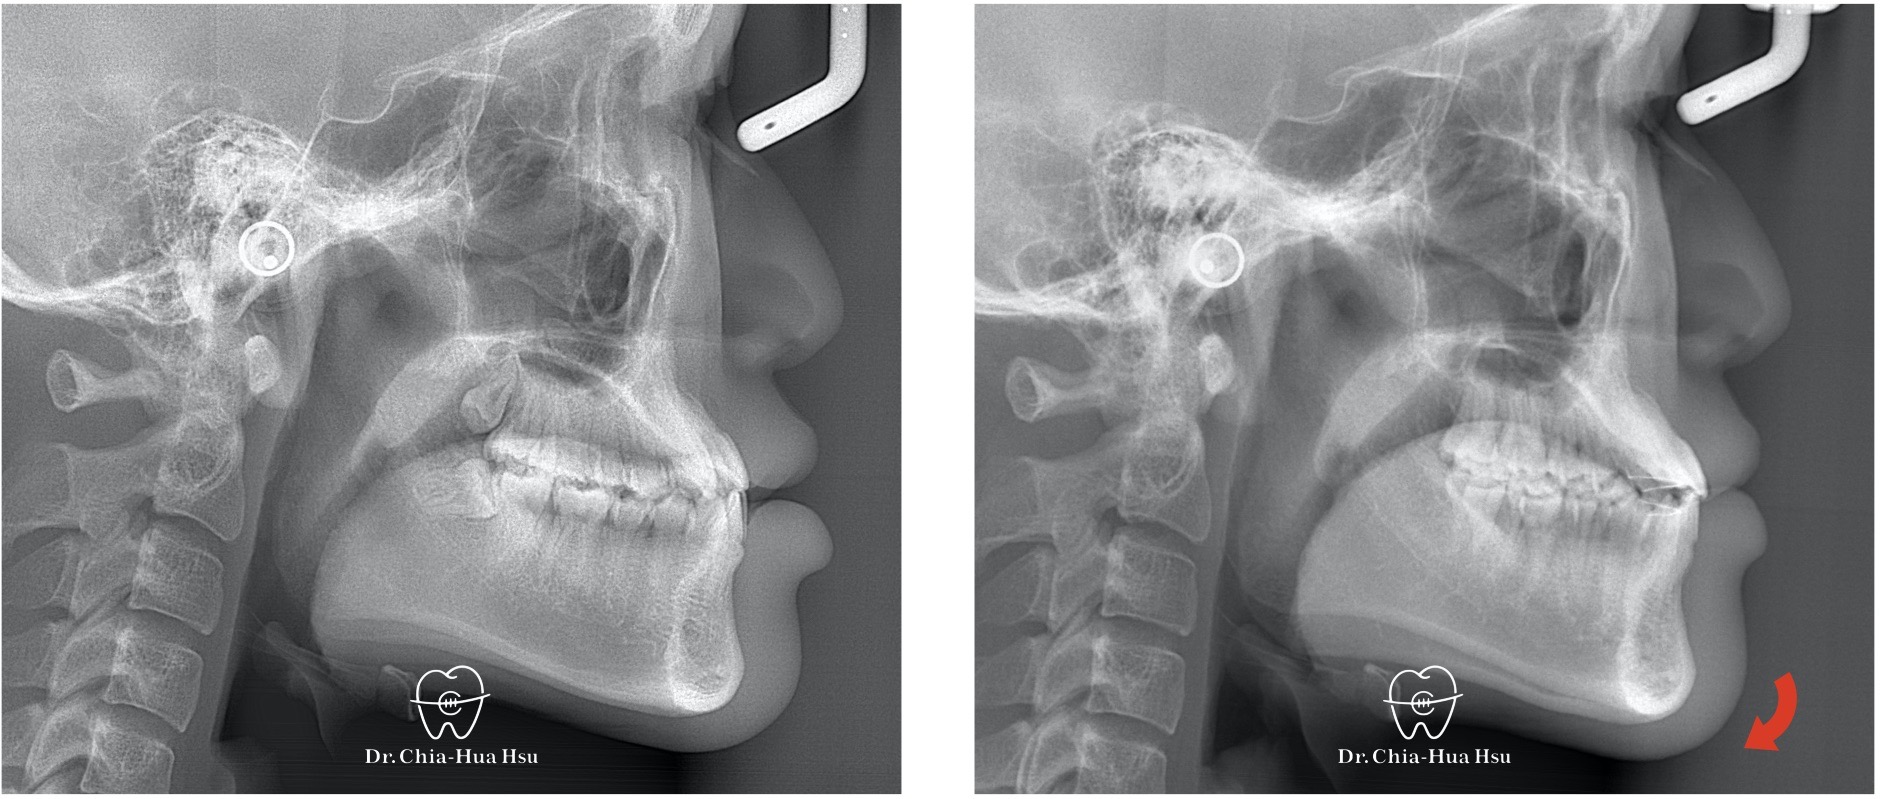

戽斗、錯咬

• 病患主訴:前牙錯咬、不整齊,有戽斗臉型,但不想做正顎手術。

• 問題分析:患者是輕微的骨骼三類咬合(Skeletal Class III)、下巴過長(戽斗)、前牙錯咬以及齒列不整齊。

• 治療方式:使用傳統金屬矯正器,並搭配垂直向橡皮筋牽引(Vertical elastics)使牙齒萌出。

• 治療結果:門牙露出增加、齒列排齊 ; 下臉部高度微增使下巴順時針微量旋轉,以修飾戽斗臉型。

治療前

治療後